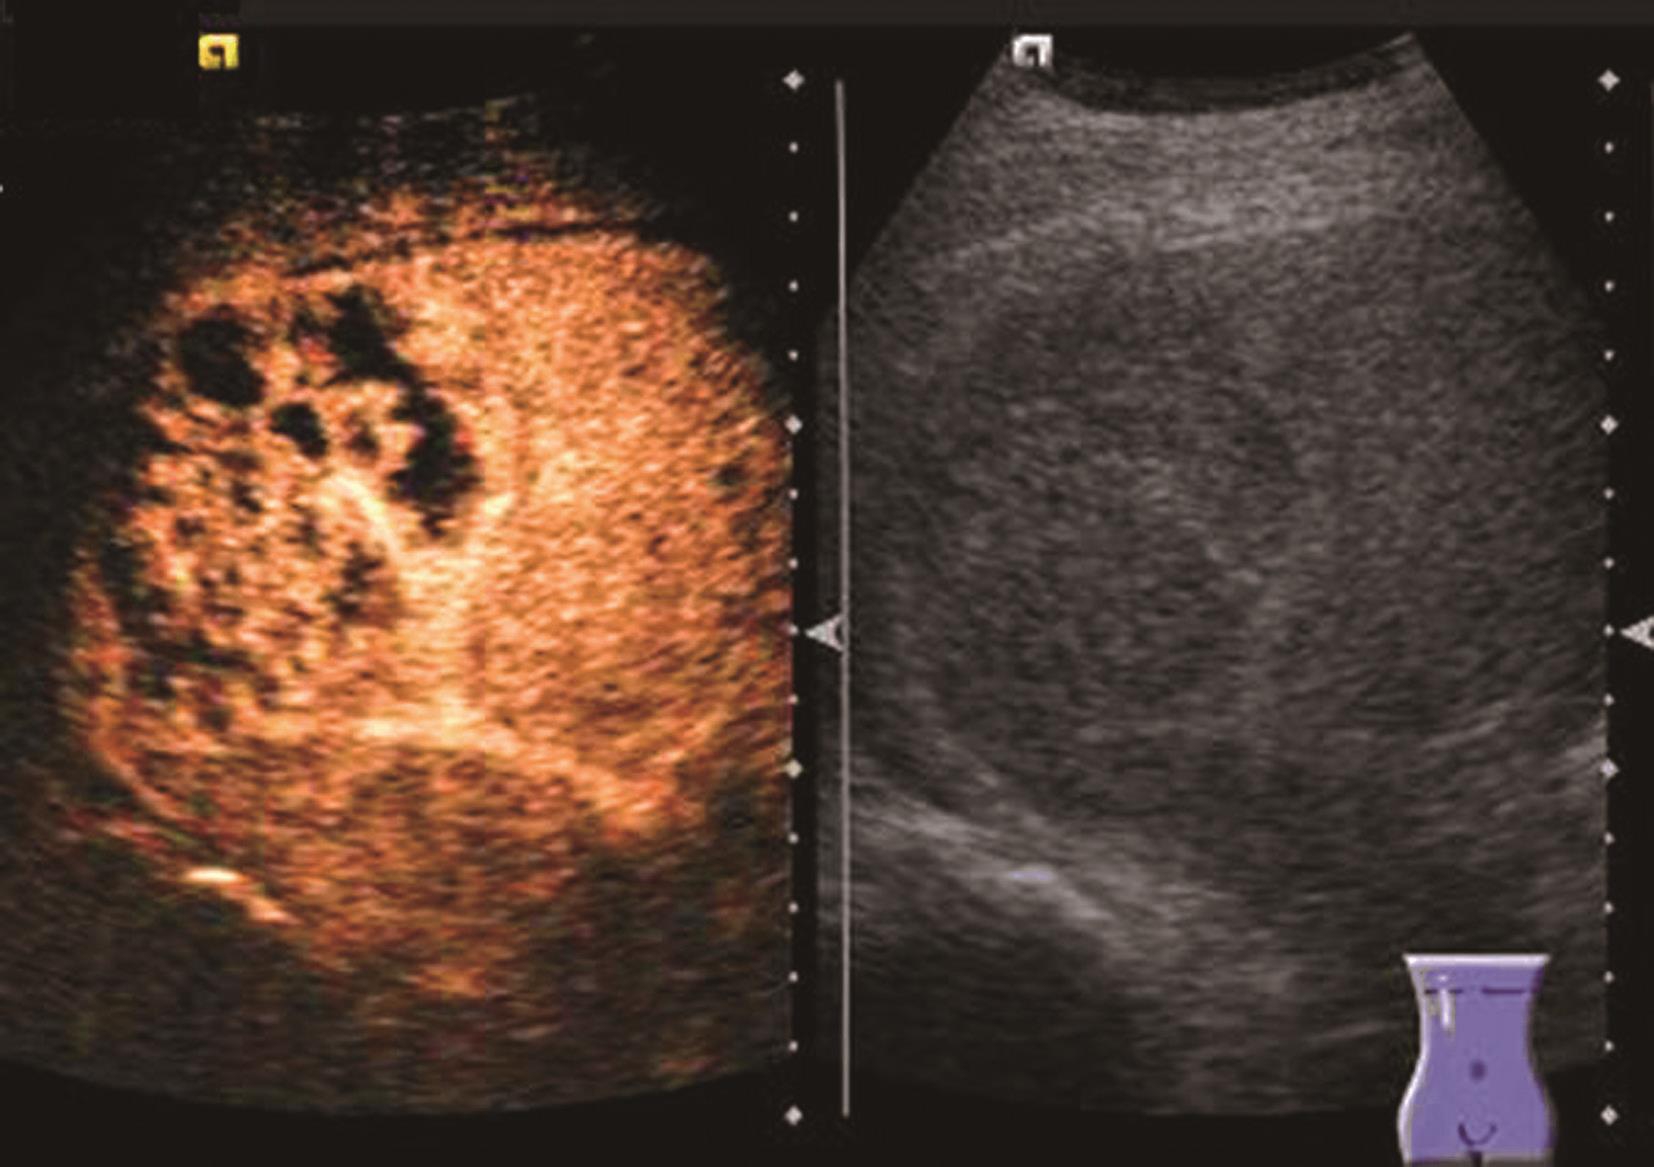

3.超声造影表现

炎症充血期,动脉期病灶整体快速蜂窝状增强,呈等增强或轻度高增强,无增强区呈细小点状无回声;脓肿形成期病灶内液性部分增大,动脉期呈簇状、蜂窝状或片状无增强区,脓腔后期成熟后可形成较大脓腔,超声造影可见不规则分隔带或“花瓣”征,实质部分门脉期及延迟期呈等增强,少数病例可轻度消退;脓肿恢复期,超声造影显示脓腔缩小,表现与脓肿早期类似,直至恢复正常。肝脓肿超声造影动脉期、静脉期及延迟期超声像图表现如图5-21-9~图5-21-11所示。

图5-21-9 肝脓肿超声造影动脉期

图5-21-10 肝脓肿超声造影静脉期

图5-21-11 肝脓肿超声造影延迟期